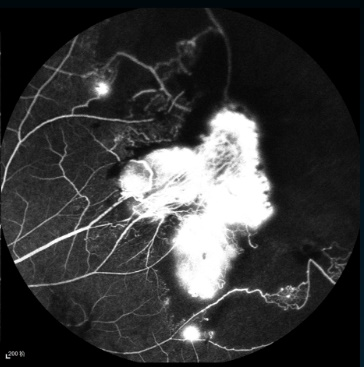

一名21岁的年轻女性,以“双眼视力下降3月余”为主诉就诊,此前已经确诊了SLE ,并且口服激素1年。但其在3月余前无明显诱因出现双眼视力急剧下降,就诊当地医院诊断为“双眼脉络膜炎”,在予药物治疗后无明显好转故就诊于我院。在对其进行眼部体查时可见其右眼裸眼视力为0.25,左眼为0.15,右眼最佳矫正视力为0.8,左眼为0.3。眼底检查双眼视网膜面见大量斑片样脉络膜病灶,自发荧光显示“黑心白边”,病灶围绕视盘,眼底荧光造影显示病灶处有荧光着染,脉络膜造影病灶显示相对应处低荧光。

实验室检查发现,患者除免疫指标存在异常,补体C3、C4水平降低外,T-SPOT检测阳性。结合以上资料,考虑患者为系统性红斑狼疮伴发双眼匍形性结核性脉络膜炎。给予其抗结核治疗以及异烟肼 0.3g Qd、利福平 0.45g Qd等治疗,治疗后患者的眼部情况好转。